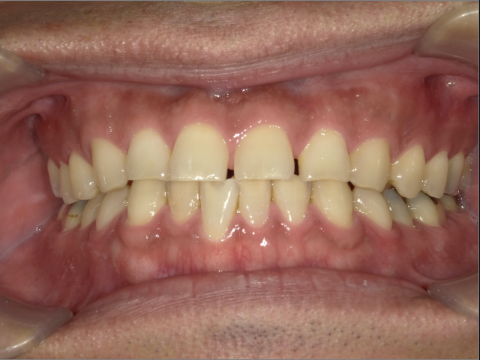

BEFORE

AFTER

ご年齢 15歳女性 治療期間 2022/07/02〜2023/12/02(1年5ヶ月)

診断 110,000円(税込) アライナー 660,000円(税込) リテーナー 55,000円(税込)

ご年齢 15歳女性

治療期間 2022/07/02〜2023/12/02(1年5ヶ月)

診断 110,000円(税込)

アライナー 660,000円(税込)

リテーナー 55,000円(税込)